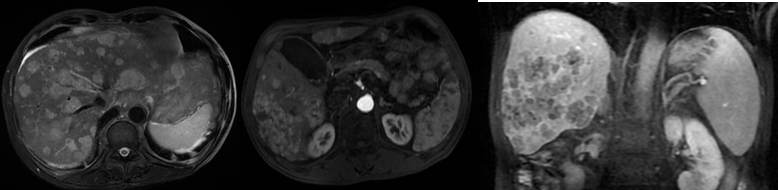

2020年2月27日上腹部CE-CT:考虑肝内多发肿瘤;肝硬化、门脉高压、脾大;增强CT提示:肝内多发肿瘤(符合原发性肝癌快进快出的影像学特征)(图1)。

图1.2020年2月27日上腹部CT